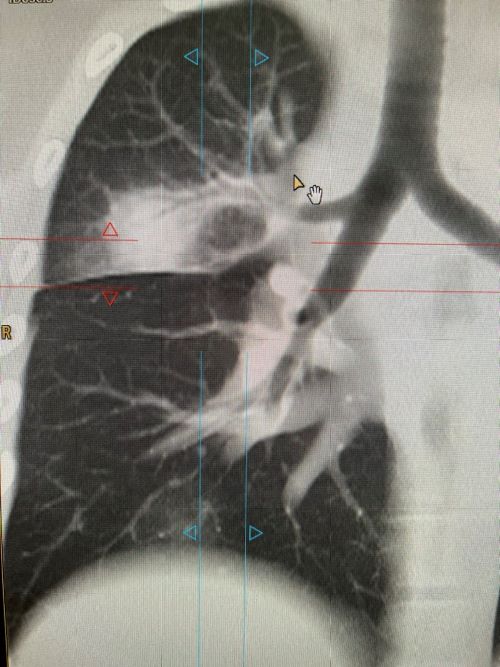

После проведённого сканирования были выявлены поражения в обоих лёгких, с выраженным инфильтратом в верхней доли правого лёгкого.

После интерпретации полученных снимков пациентке выставлен диагноз: Двустроронняя полисегментарная пневмония. Лимфоаденопатия ВГЛУ. Образование ? в верхней доле правого лёгкого.

По окончании лечения рекомендовано контрольное обследование на МСКТ для исключения новообразования.